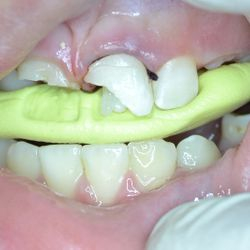

This 9-years old girl fractured her upper central incisors in an accident.

The teeth were root-treated and then restored to form and function using latest technology composite fillings restorations re-enforced with aesthetic fiber posts in a single appointment.

The smile of our little patient was back on her face in no-time!